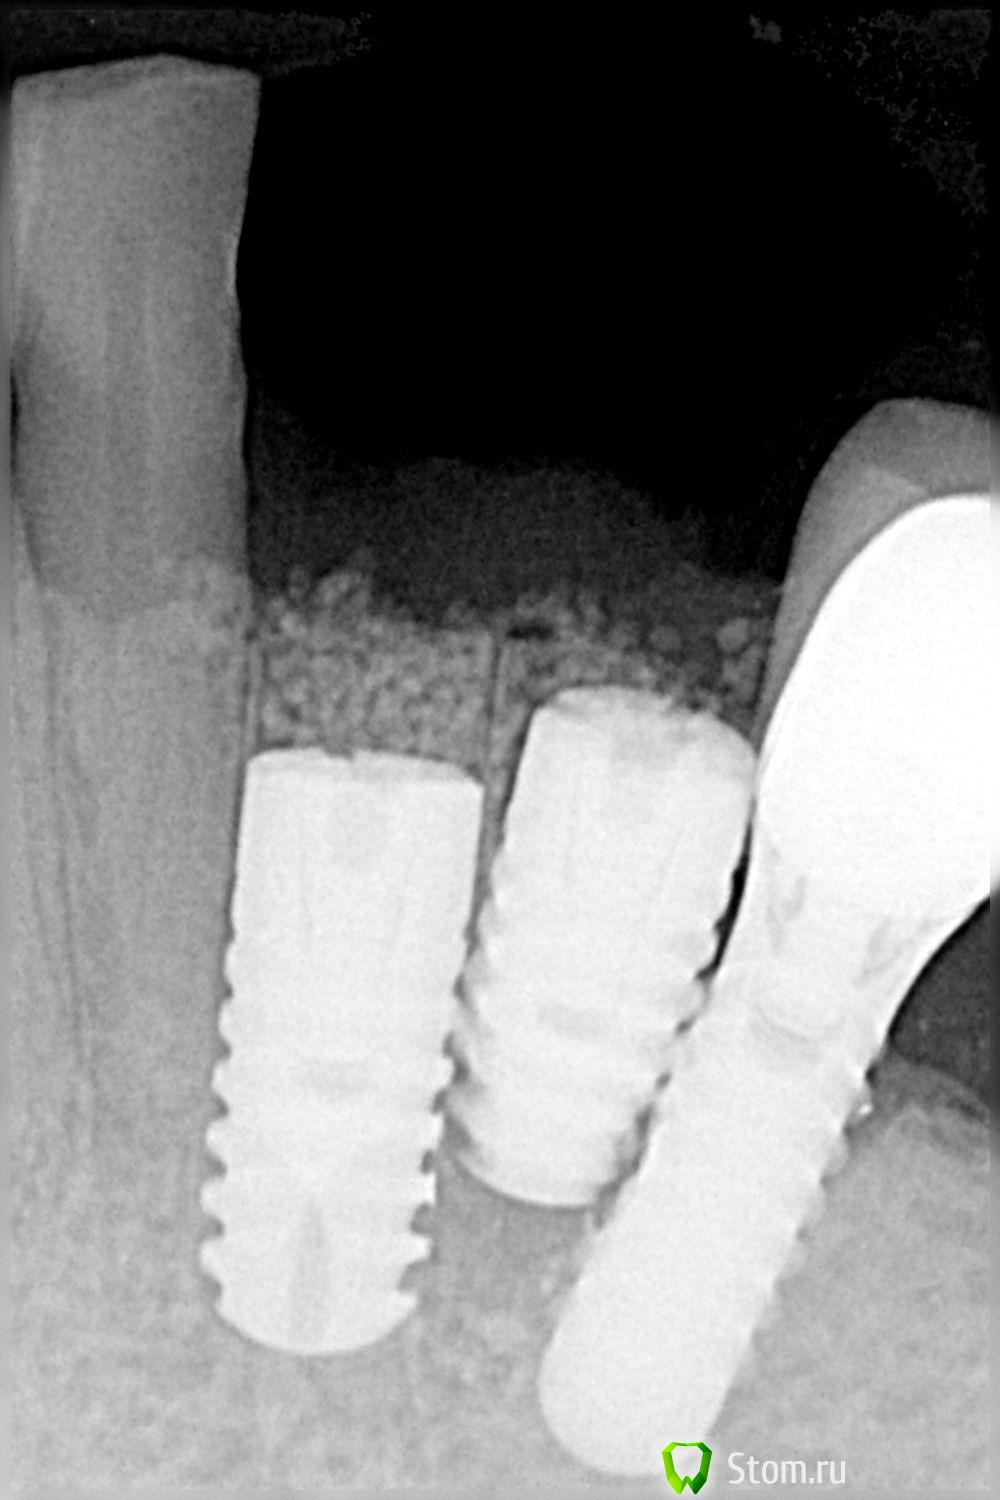

FBR Опубликовано 20 марта, 2012 Поделиться Опубликовано 20 марта, 2012 Формирователь справа расклинен и недокручен. По протезированию большой вопрос. Хотелось бы прямую речь техника услышать после анализа работы... Ссылка на комментарий

Doc Опубликовано 20 марта, 2012 Поделиться Опубликовано 20 марта, 2012 Формирователь справа расклинен и недокручен. По протезированию большой вопрос. Да там вообще странно, подпилили с одной стороны, а закрутили другой. Естественно, что формирователь не сел. Ссылка на комментарий

Sib-oboima Опубликовано 20 марта, 2012 Автор Поделиться Опубликовано 20 марта, 2012 Я в эту работу больше не лезу, формирователь не докручен-согласен, еще раз повторюсь на мою просьбу ставить длинее формирователи, да и в общем все что с этим связано, ответ всегда один(все нормально, так должно быть, если бы в крутил полностью было бы не совсем хорошо) примерно так. Заходил в лабораторию техник матерясь что-то колдует(делает м/к), в субботу уже сдача, снимки сделаю. Я не доволен всем происходящим. Ссылка на комментарий

FBR Опубликовано 21 марта, 2012 Поделиться Опубликовано 21 марта, 2012 (изменено) Я в эту работу больше не лезу, формирователь не докручен-согласен, еще раз повторюсь на мою просьбу ставить длинее формирователи, да и в общем все что с этим связано, ответ всегда один(все нормально, так должно быть, если бы в крутил полностью было бы не совсем хорошо) примерно так. Заходил в лабораторию техник матерясь что-то колдует(делает м/к), в субботу уже сдача, снимки сделаю. Я не доволен всем происходящим.Я хоть сам и хирург (протезировать только начал), но в данном случае можно было рассмотреть вариант консольной нагрузки на имплант (полхой конечно вариант, но вариант по моему). Либо поставить 2, но тоньше. А на самом деле в такой ситуации надо брать ортопеда и ставить на операции рядом чтобы потом вопросов не возникало. Изменено 21 марта, 2012 пользователем FBR 1 Ссылка на комментарий

FBR Опубликовано 21 марта, 2012 Поделиться Опубликовано 21 марта, 2012 ПРО ортопеда рядом, хотя время скорей всего не позволит этого сделатьТогда от них либо шаблон либо стоять рядом. Если нет тады ой. Ну а про этот случай можно сказать, что планирование отсутствует полностью (хотя бы слепки обсудить) , ну и хирург куда смотрел, то же вопрос. Удивительно что резорбция кости не началась.... Ссылка на комментарий

Doc Опубликовано 21 марта, 2012 Поделиться Опубликовано 21 марта, 2012 Тогда от них либо шаблон либо стоять рядом. Если нет тады ой. Ну а про этот случай можно сказать, что планирование отсутствует полностью (хотя бы слепки обсудить) , ну и хирург куда смотрел, то же вопрос. Зачем стоять рядом? Дается шаблон и все дела. Один раз хирург обязательно все спишет на условия. Второй раз нужно объяснить хирургу, что шаблон дается не просто так, а для того, чтобы ставили именно по нему. В третий раз нужно менять хирурга. Вы не сможете и не должны ВСЮ ЖИЗНЬ стоять с ним рядом и с боем добиваться правильной установки. В конце концов Вам проще либо поменять хирурга, либо уж самому научиться ставить имплантаты, если хирург настолько туп, что не понимает элементарного протокола. Удивительно что резорбция кости не началась.... Она уже началась. Просто ее пока не видно. Ссылка на комментарий